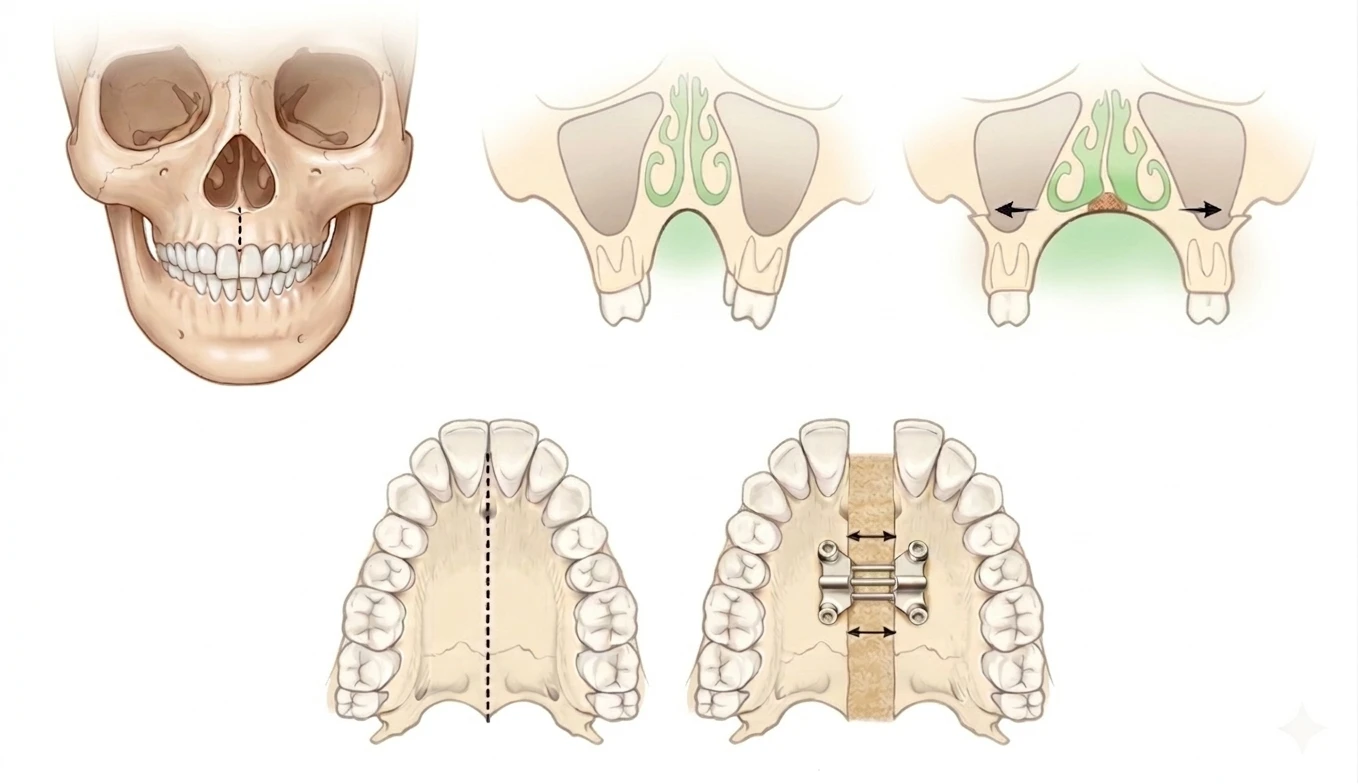

Why the Midpalatal Suture Matters in Adults

The midpalatal suture is the seam that joins the right and left halves of the upper jaw and plays a major role in how the upper arch responds to expansion. In adults, this area is usually more interlocked, denser, and more resistant than it is in younger patients, which means conventional tooth-borne expansion may produce more dental tipping and less true skeletal widening. Because adult skeletal anatomy is more mature, selected cases may require MARPE to direct force more effectively toward the suture and supporting bone, improving the potential for meaningful transverse correction and more stable width development.

How Traditional MARPE works:

In a traditional MARPE workflow, skeletal expansion is typically completed before detailed alignment begins. As the midpalatal suture separates, a visible space may develop between the upper central incisors during active expansion, with orthodontic alignment sequenced afterward to close and coordinate that space.

By sequencing treatment this way, the space that opens between the front teeth is often managed more actively than it is in a traditional expansion-first workflow. The goal is to support skeletal correction while keeping the dental response more controlled, improving arch coordination as expansion progresses, and reducing the need for a separate large-gap phase before alignment begins.